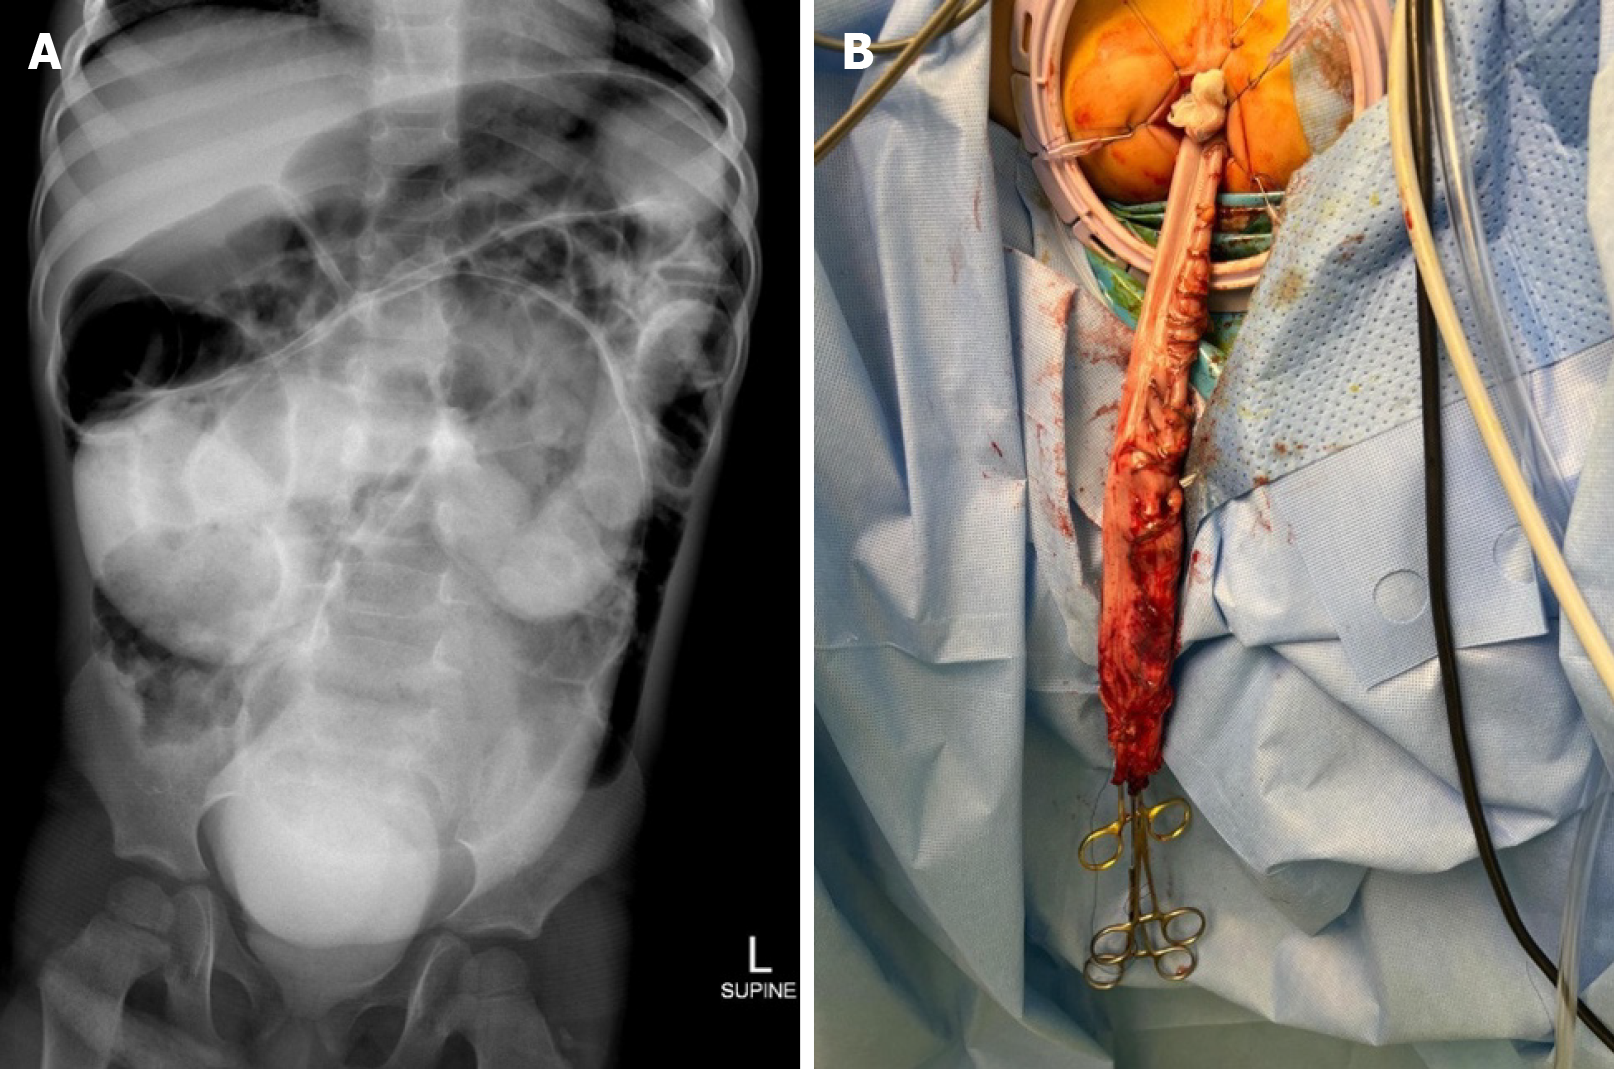

Figure 1 Radiological and surgical images from Case 1.

A: Rectally administered contrast revealed opacity and a markedly distended colonic structure in the central abdomen and pelvis; B: The distal sigmoid colon was pulled down from the anal verge as a part of a laparoscopic pull-through procedure.